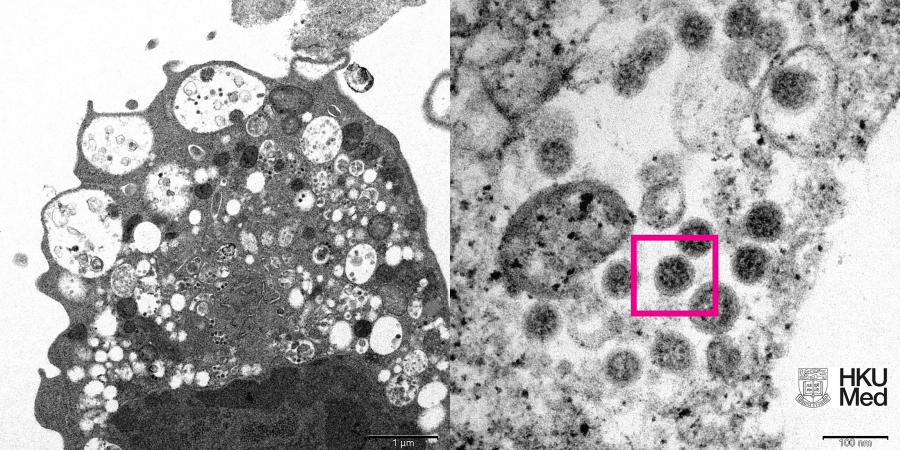

(圖左)低倍電子顯微鏡下感染新型冠狀病毒Omicron變異株後的猴腎細胞(Vero E6)。照片顯示細胞受損,腫脹囊泡,囊泡內含有黑色小病毒顆粒。

(圖右)高倍電子顯微鏡下受感染的Vero E6細胞。照片顯示病毒顆粒,其表面呈現皇冠形的刺突蛋白(見紅框)。

照片來源:香港大學李嘉誠醫學院(港大醫學院)病理學系臨床教授黎國思教授、公共衞生學院譚華正基金教授(醫療科學)兼病毒學講座教授裴偉士教授,及香港大學電子顯微鏡研究所。